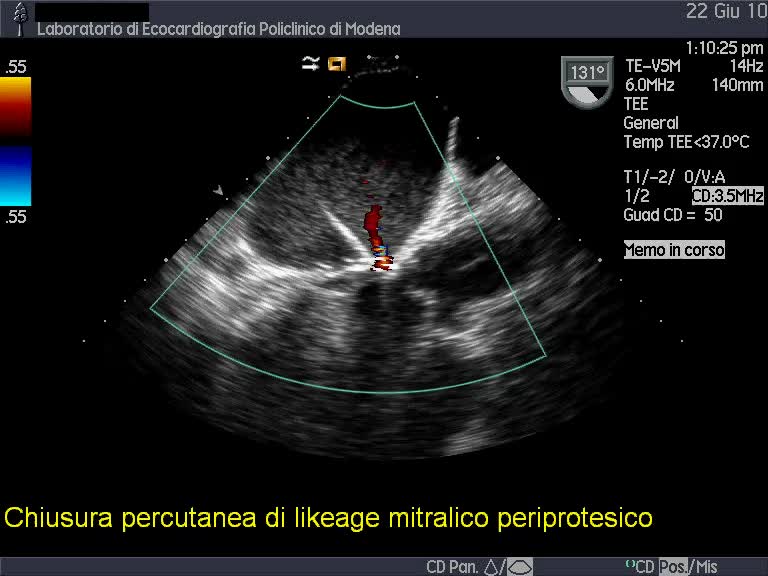

Chiusura percutanea di paraleak (protesi valvolare mitralica biologica)

Autore:

Andrea Barbieri